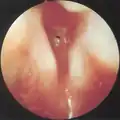

Subglottic stenosis is graded according to the Cotton-Myer classification system from one to four based on the severity of the blockage. Grade 1 is up to 50% obstruction, Grade 2 is 50-70% obstruction, Grade 3 is 70-99% obstruction, and Grade 4 is with no visible lumen.[5]

-

Grade 1 subglottic stenosis -

Grade 2 subglottic stenosis -

Grade 3 subglottic stenosis -

Grade 4 subglottic stenosis